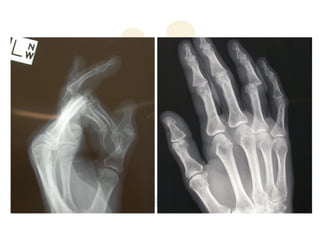

PIPJ dislocations

Dorsal PIPJ Dislocation

Dorsal PIPJ Dislocations

ď‚§ Mechanism: PIPJ hyperextension combined with

some degree of longitudinal compression

ď‚§ Frequently occurs in ball-handling sports

ď‚§ Usually produces soft tissue or bone injury to the

distal insertions of the 3D ligament-box complex.

ď‚§ The greater the longitudinal force, the more

likelihood for fracture dislocation

ď‚§ Rarely, VP ruptures volarly & become interposed

within the PIPJ causing irreducible dislocation

ď‚§ Volar fracture may even become trapped within the

flexor sheath and inhibit motion.

ď‚§ Type I (hyperextension): VP

avulsed; incomplete

longitudinal split in col. ligs.;

articular surfaces remain

congruous.

ď‚§ Type II (dorsal dislocation):

complete rupture VP; complete

split in col. ligs.; MP resting on

dorsum of PP.

ď‚§ Type III (fracture-dislocation):

disruption at the volar base of

MP where VP is inserted; stable

vs unstable injuries